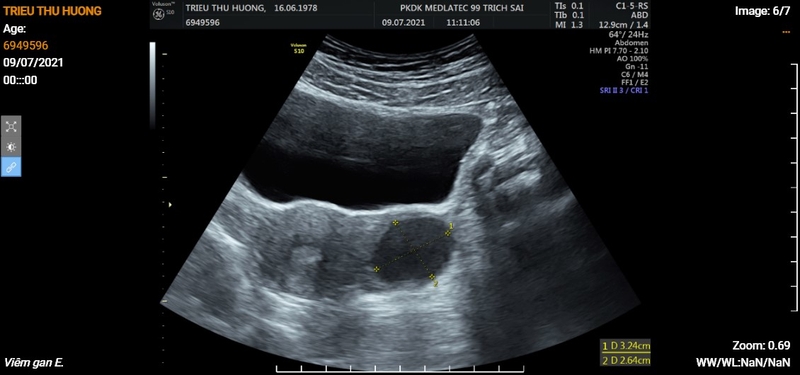

Thông thường, bạn sẽ được chỉ định siêu âm ổ bụng khi đi khám sức khỏe định kỳ. Ngoài ra, trường hợp nếu bác sĩ nghi ngờ bệnh nhân có khả năng mắc bệnh ở các cơ quan khu vực ổ bụng thì cũng sẽ cho thực hiện siêu âm bụng để chẩn đoán chính xác tình trạng bệnh.

Như đã đề cập bên trên, ai cũng nên thực hiện việc siêu âm ổ bụng định kỳ để bảo vệ sức khỏe bản thân. Bên cạnh đó, những người có nhu cầu kiểm tra khi có dấu hiệu bất thường đều hoàn toàn có thể thực hiện việc siêu âm bụng tổng quát. Thông qua việc siêu âm ổ bụng, bác sĩ sẽ kiểm tra tất cả các bộ phận bao gồm mật, gan, hệ sinh dục nữ - nam, hệ tiết niệu,… để đánh giá tình hình sức khỏe. Ngoài ra, một số trường hợp đặc biệt khi tiến hành kỹ thuật nhỏ ở khu vực này, bác sĩ sẽ chỉ định siêu âm ổ bụng nhằm giúp thao tác được chính xác và chuẩn vị trí hơn.